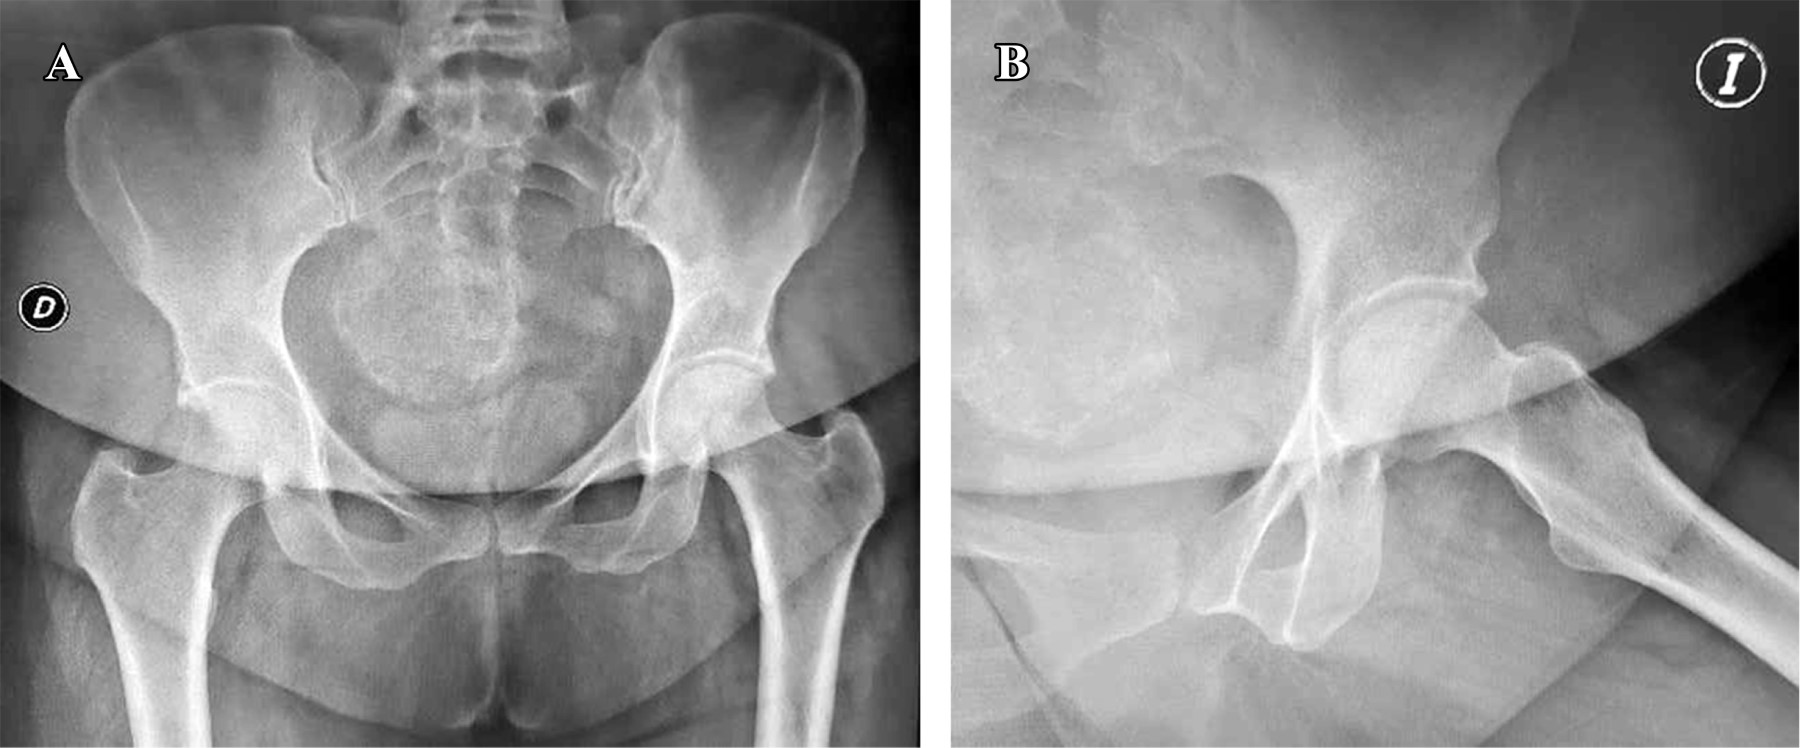

Todos los pacientes habían recibido corticosteroides como parte de su régimen de tratamiento para COVID-19 con dosis promedio de 480 mg, en un rango de 400 a 1,200 mg de hidrocortisona (o su equivalente –se adjunta tabla de conversión–) (Tabla 1). Estos pacientes mostraron síntomas clásicos de NAVCF caracterizados por un rápido deterioro funcional con sintomatología clínica de dolor, limitación a la carga y movilización. Asimismo, presentaron los cambios correspondientes en las imágenes de radiografías y resonancia magnética nuclear (RMN); los estadios de necrosis fueron clasificados según Ficat8 (Figuras 1 y 2). Se incluyeron estadios I a III de la clasificación dada la juventud de la serie y que no tenían artrosis con disminución del espacio articular.

Con base en la evaluación radiografía y de resonancia magnética nuclear, los pacientes fueron organizados de acuerdo con la clasificación de Ficat: estadio I, 10 (47.6%) casos; estadio II, seis (28.6%) casos y estadio III, cinco (23.8%) casos (Tabla 2).

En los casos restantes, no se observó progresión adicional del daño de la cabeza femoral, logrando así una supervivencia de 85.4% (Figuras 6 y 7).